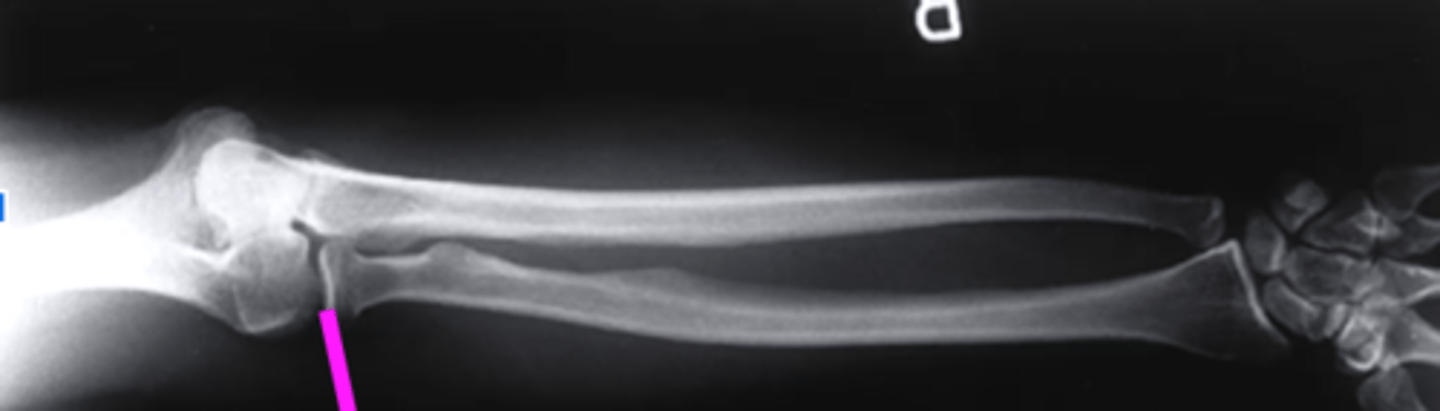

lateral forearm

what view is this

olecranon process

what does this pink line point to?

ulna

radius

radiocarpal joint